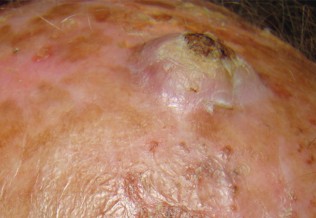

Carcinome basocellulaire

Impétigo

Gale de l’enfant

Formes cliniques du psoriasis